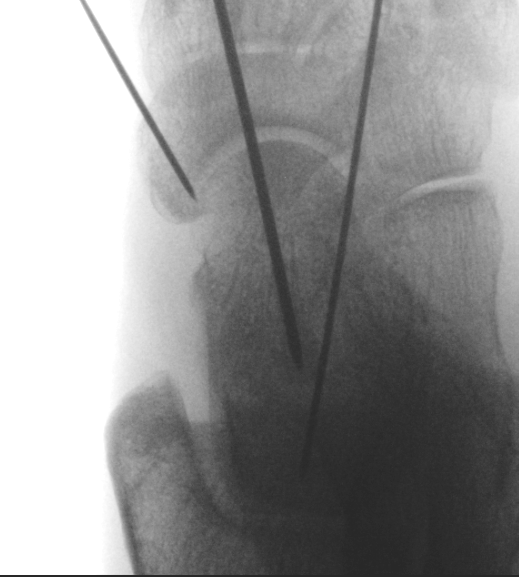

Cannulated screws

Xrays

| AP | Lateral | Canale View |

|---|---|---|

| Entry point of the screws |

Evaluate neck reduction

|

Evaluates the neck reduction |

Lateral off articular surface Medial through articular cartilage |

Depth of screws |

Beam angled 75o to foot Foot 15o pronated |

1. Retrograde (anterior to posterior) into posterior talus body

A. Lateral screw

- insert proximal to articular surface of head on lateral side

- bone is very curved here

- can lag screw as usually no comminution

B. Medial side

- insert through articular surface

- countersunk screws through articular surface

- avoid lag screw techniques medially as may compress comminution into varus

AP, Canale and Lateral xray

Retrograde screws